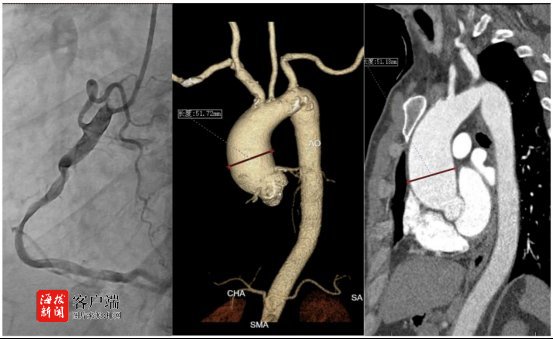

入院后,心外科团队迅速为陈先生进行了详细检查评估。在严飞主任团队、符川医生(心脏超声)、洪超医生(主动脉三维成像)以及心内科冠脉造影团队的紧密协作下,陈先生的病情很快明确:

1主动脉瓣回声增强,重度狭窄(瓣口面积仅0.8cm²,远低于正常值);

2升主动脉瘤样扩张(最宽处直径达52mm,远超正常上限);

3.右冠状动脉中段存在严重狭窄(60—70%),近段狭窄30%。